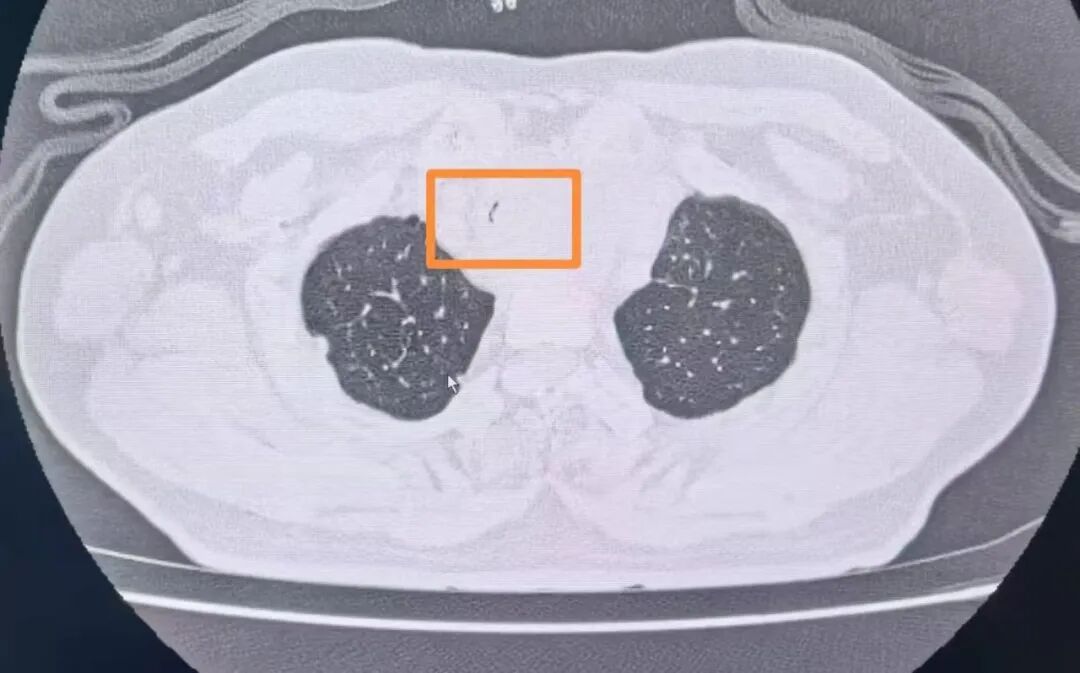

經(jīng)復(fù)查胸部CT發(fā)現(xiàn)患者氣管已經(jīng)出現(xiàn)明顯狹窄,內(nèi)徑最窄處直徑不到2mm(正常成年男性氣管內(nèi)徑為18-22mm),呈“一線天”樣改變,整個(gè)氣管僅靠一條細(xì)微的縫隙維持著少量的通氣,意味著病人隨時(shí)有發(fā)生窒息的危險(xiǎn)。甲乳外科立即組織開展了多學(xué)科討論。經(jīng)過對(duì)病情的充分分析,呼吸與危重癥醫(yī)學(xué)科副主任陳暉建議緊急行氣管內(nèi)支架置入術(shù)解除大氣道梗阻。